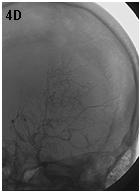

Mujer de 46 años que ingreso por cefalea súbita, hemiparesia izquierda y disartria, con tomografía axial computarizada cerebral simple que mostró hemorragia frontoparietal derecha drenada a ventrículos y arteriografía con patrón Moyamoya. Reingreso 3 meses después con deterioro del estado de consciencia y tomografía axial computarizada cerebral simple que mostró hemorragia intraparenquimatosa temporoparietal izquierda con extensión intraventricular y desviación de la línea media, se manejo en Unidad de Cuidados Intensivos con traqueostomía y gastrostomía, presentó neumonía y sepsis nosocomial, finalmente falleció en la Unidad de Cuidados Intensivos.